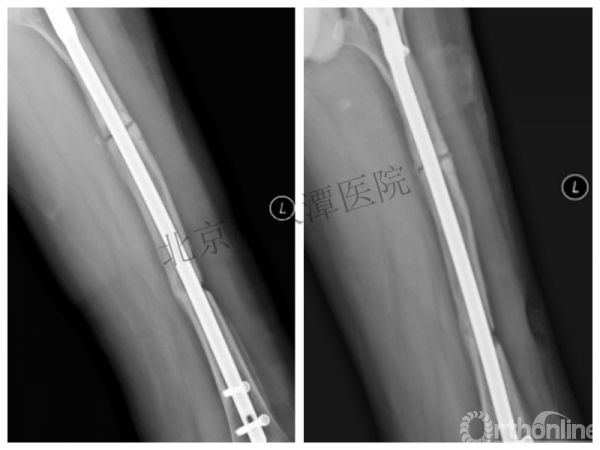

取板后再骨折→TEN

TEN取出后2个月

闭合复位再固定加尾帽

又过了4年!时间来到2015年

一年以后顺利愈合,实则危机四伏

数月后再骨折!牵引!